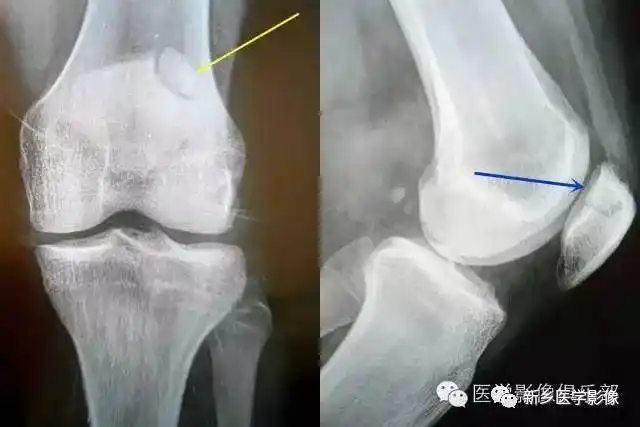

连接处可见一低密度弧状偷明线,宽窄均匀,边缘硬化轴位显示髌骨分左右